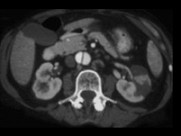

男,54岁,请根据所示图像,选择最可能诊断 ( ) XL-90171.jpg XL-90172.jpg

题型: 多选题 分类: 肾内科

• A.主动脉夹层

• B.左侧肾积水

• C.左侧肾梗死

• D.左侧肾脓肿

• E.左侧肾囊肿